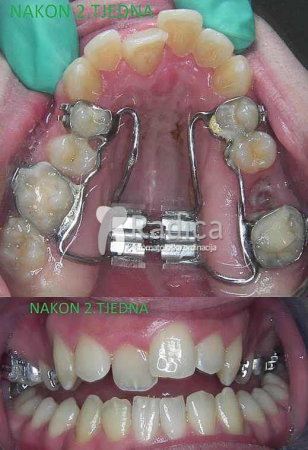

Hyrax se pomoću prstene fiksira na prve trajne molare i prve premolare. Vijak se okreće svaki dan i već nakon par dana se vidi učinak jer se pojavljuje razmak između sjekutića. Nakon dva tjedna se vijak blokira i aparat ostaje u ustima najmanje sljedećih 4-6 mjeseci. Fiksni aparat se obično stavi nakon tri mjeseca. Hyrax ima najbolji efekt u vrijeme mješovite denticije – najčešće između 9-12 godine.

U sljedećim galerijama možete vidjeti primjere upotrebe Hyraxa:

1. primjer